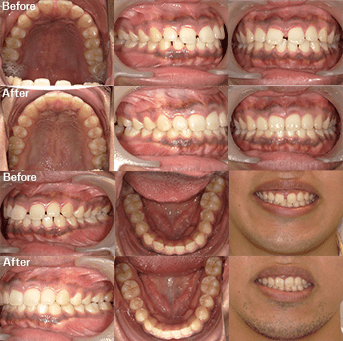

治療方法 【矯正】インビザライン、光加速装置「PBM HEALING」

【ホワイトニング】

ホワイトエッセンスコース

(オフィスホワイトニング※1 3回、ホームホワイトニング 2か月分、クリーニング※2 2回、特選ホームケア用品)治療の説明 主訴: 前歯が出てる、下の歯のがたつき 年齢 24歳 ![]()

治療費用 1,054,000円(税込)、相談・検査・診断料・調整料:無料 治療期間 【矯正】1年10か月 通院回数 【矯正】 18回

【ホワイトニング】期間・回数:治療内容により異なります治療の副作用(リスク) 【矯正】咬合痛、歯根吸収、歯根露出が生じる可能性があります。

【ホワイトニング】個人差がありますが、施術中や施術後に歯がしみる場合があります。

保証制度:040 の白さに達成するまで追加で施術を受けられる制度です。万が一040 に達しない場合は、材料費を差し引いた70,000 円を返金します。

※テトラサイクリン薬剤による変色は保証の対象外です。

※差し歯等でない限り、右上の前歯が保証対象歯です。

中途解約制度:あり

※1 オフィスホワイトニング プロプラス

※2 オーラルスパクリーニング、ナノアパタイトコート研磨歯科医師からのコメント 頬側拡大を行い、上顎前歯の突出感を改善。追加アライナーでは残存空隙利用と少し遠心移動を追加して咬合を調整しています。